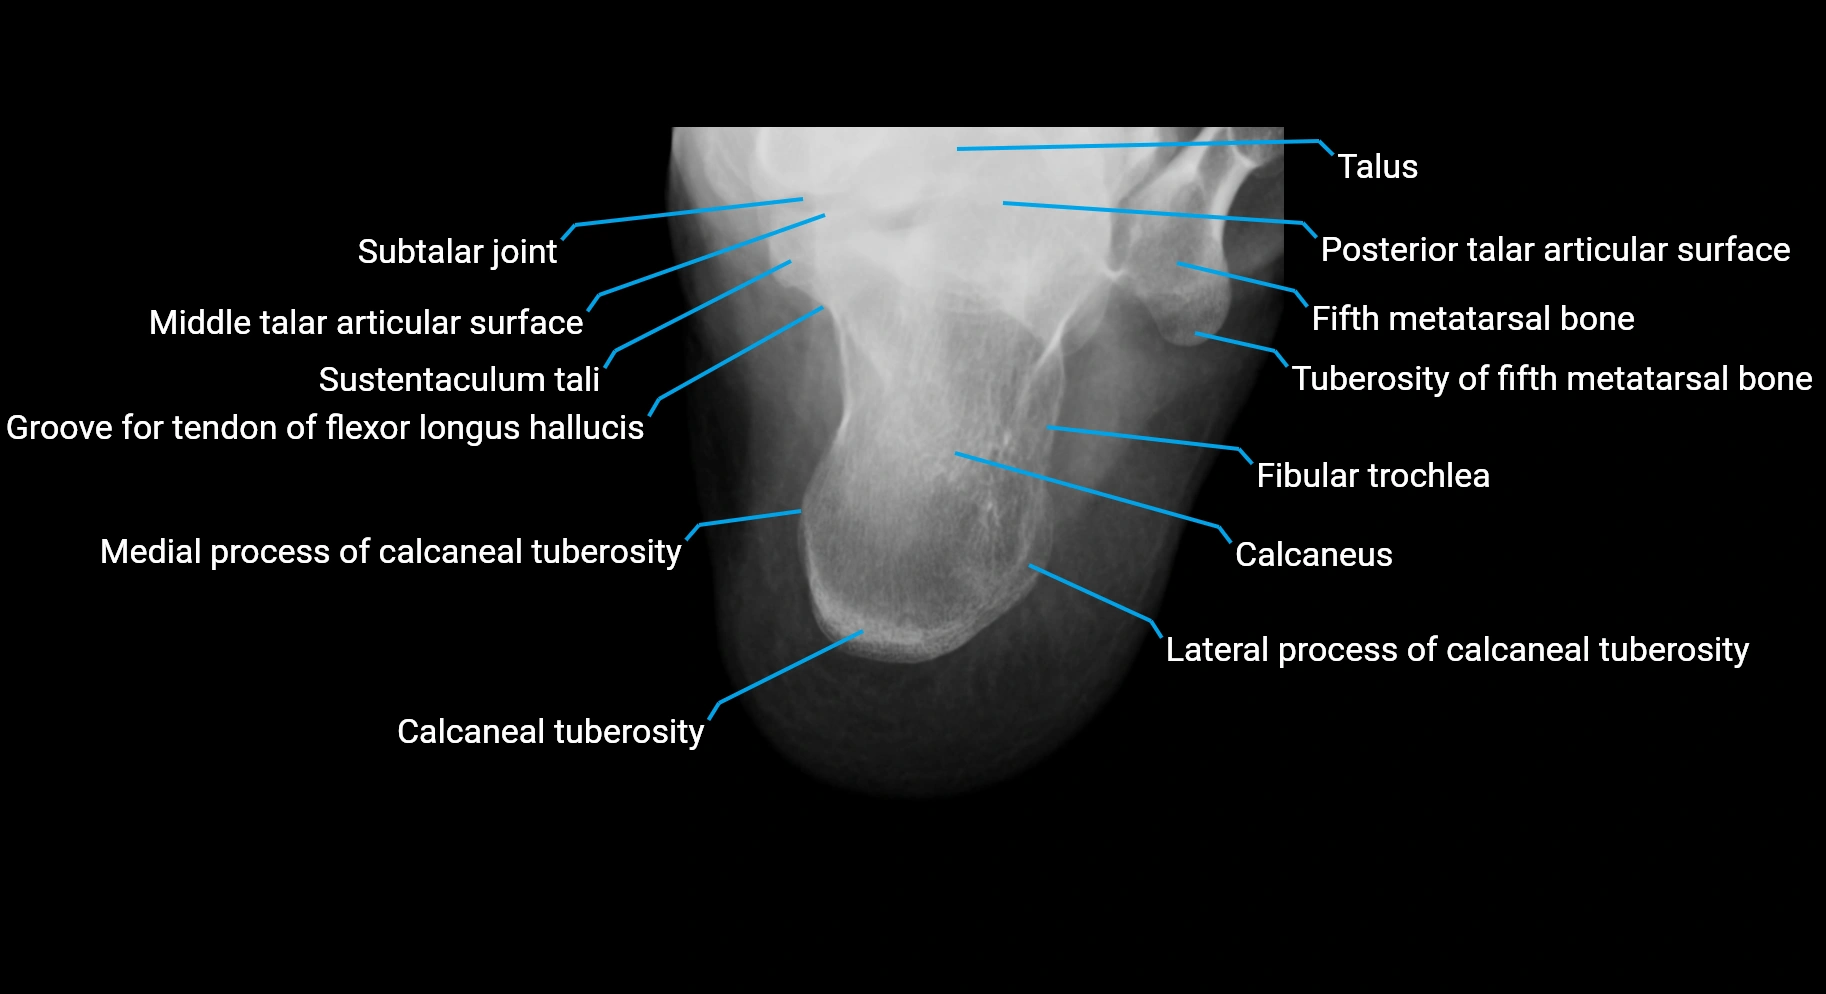

CT image

image